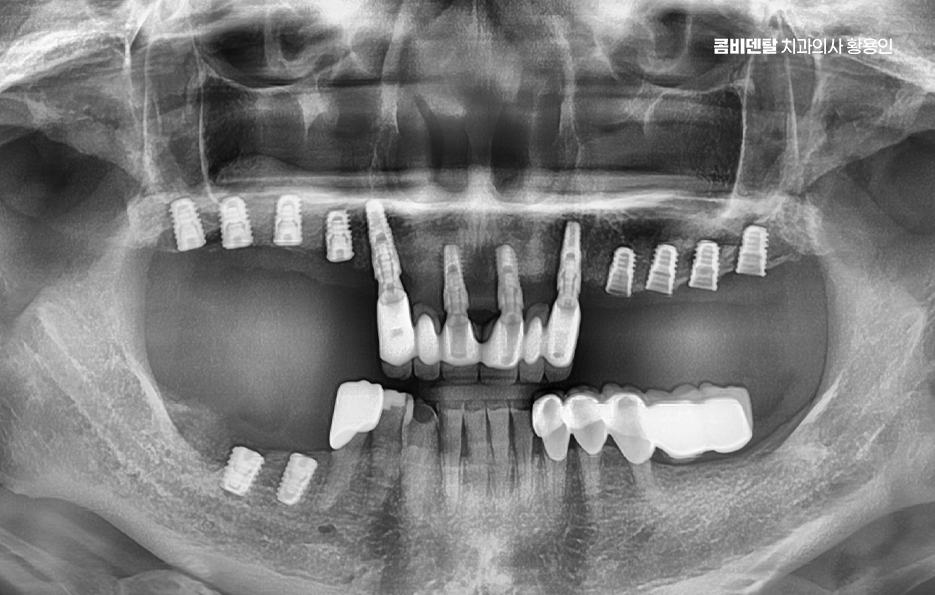

어금니 임플란트 치료 시 먼저 고려해야 할 주의사항은 뼈의 상태로 임플란트는 뼈에 직접 고정되는 구조이기 때문에, 뼈의 양과 질이 충분하지 않으면 안정적인 고정이 어렵고 특히 어금니 부위는 발치 후 뼈 흡수가 빠르게 진행되는 경향이 있어서, 오랜 기간 방치한 경우에는 임플란트를 바로 심기 어려운 상황이 될 수도 있었어요

이제 어금니 임플란트 뼈이식이 필요한 케이스에 대해 좀더 알아보면 뼈이식은 임플란트를 심기 위한 뼈가 부족할 때, 뼈의 양이나 형태를 보완하기 위해 시행되는 치료로서 많은 분들이 뼈이식에 대해 부담과 걱정을 느끼시곤 하는데 뼈이식은 임플란트를 더 안전하게 하기 위한 준비 과정이라고 이해하는 것이 좋을 거예요

어금니 임플란트 뼈이식 필요한 대표적 케이스는 어금니를 뽑은 지 오래된 경우로 치아가 빠진 뒤에는 그 자리를 채우던 뼈가 더 이상 필요 없다고 인식하고 점점 흡수되며 치주 질환으로 인해 어금니를 상실한 경우도 뼈이식이 필요한 경우가 많은데 치주 질환은 잇몸뿐 아니라 치아를 지지하는 뼈까지 함께 파괴하기 때문에, 발치 당시 이미 뼈가 상당히 소실된 상태인 경우가 많을 수 있었어요

상악 어금니의 경우에는 상악동이라는 구조도 고려해야 하며 위쪽 어금니 위에는 상악동이라는 빈 공간이 있는데 치아를 뽑고 시간이 지나면 이 공간이 아래로 내려오면서 임플란트를 심을 공간이 줄어들 수 있고 이런 경우에는 상악동 거상술이라는 수술과 함께 상악동 쪽 뼈를 보완하는 방식의 뼈이식이 필요해질 수 있었어요.

뼈이식이 필요하다고 해서 모두 같은 방식으로 진행되는 것은 아니며 부족한 뼈의 양과 위치에 따라 치료 방법과 범위는 달라지며 소량의 보완만 필요한 경우에는 임플란트를 심으면서 동시에 진행되기도 하고, 뼈 상태가 많이 부족한 경우에는 일정 기간 뼈가 자리 잡을 시간을 갖고 나서 임플란트를 진행하기도 해서 이 과정은 개인 상태에 따라 달라지기 때문에, 획일적으로 생각하기보다는 맞춤 계획으로 접근해야 하는 거예요